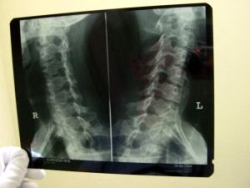

Ide o ochorenia, ktoré si na úspešné stanovenie diagnózy a liečbu vyžadujú multidisciplinárny prístup viacerých špecialistov (ortopéd, neurológ, reumatológ, FRO lekár, neurochirurg, rádiológ, internista, chirurg, urológ, gynekológ). Súčasťou vyšetrenia je dôkladné odobranie anamnézy, samotné vyšetrenie pacienta, doplňujúce zobrazovacie vyšetrenia (RTG, CT, MRI), prípadne ďalšie konziliárne vyšetrenia.